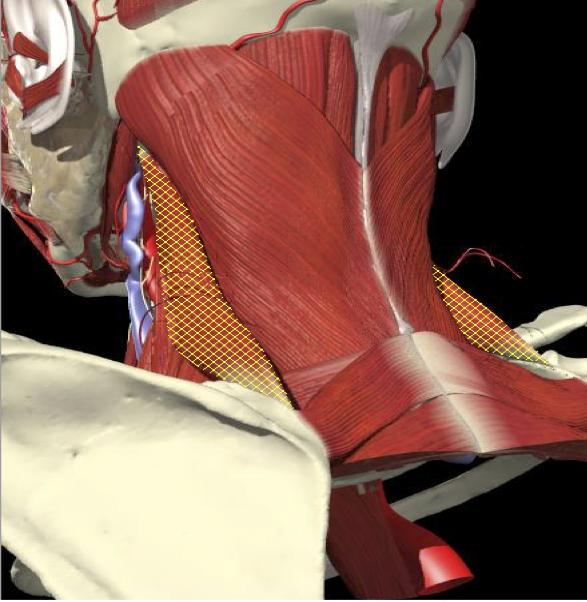

LATEROCOLLIS

Long muscles transversing spine

- Levator scapulae

- Scalenus Anterior/medius

- Semispinalis cervicis

- Longissimus cervicis

Biomechanical advantage

- Range - 37 degrees

ACCURACY OF LOCALIZATION LEVATOR SCAPULAE

LOCALIZATION OF MUSCLES IN DEEPER LAYERS

ACCURACY OF LOCALIZATION – DEEPER LAYERS

INJECTION SITES